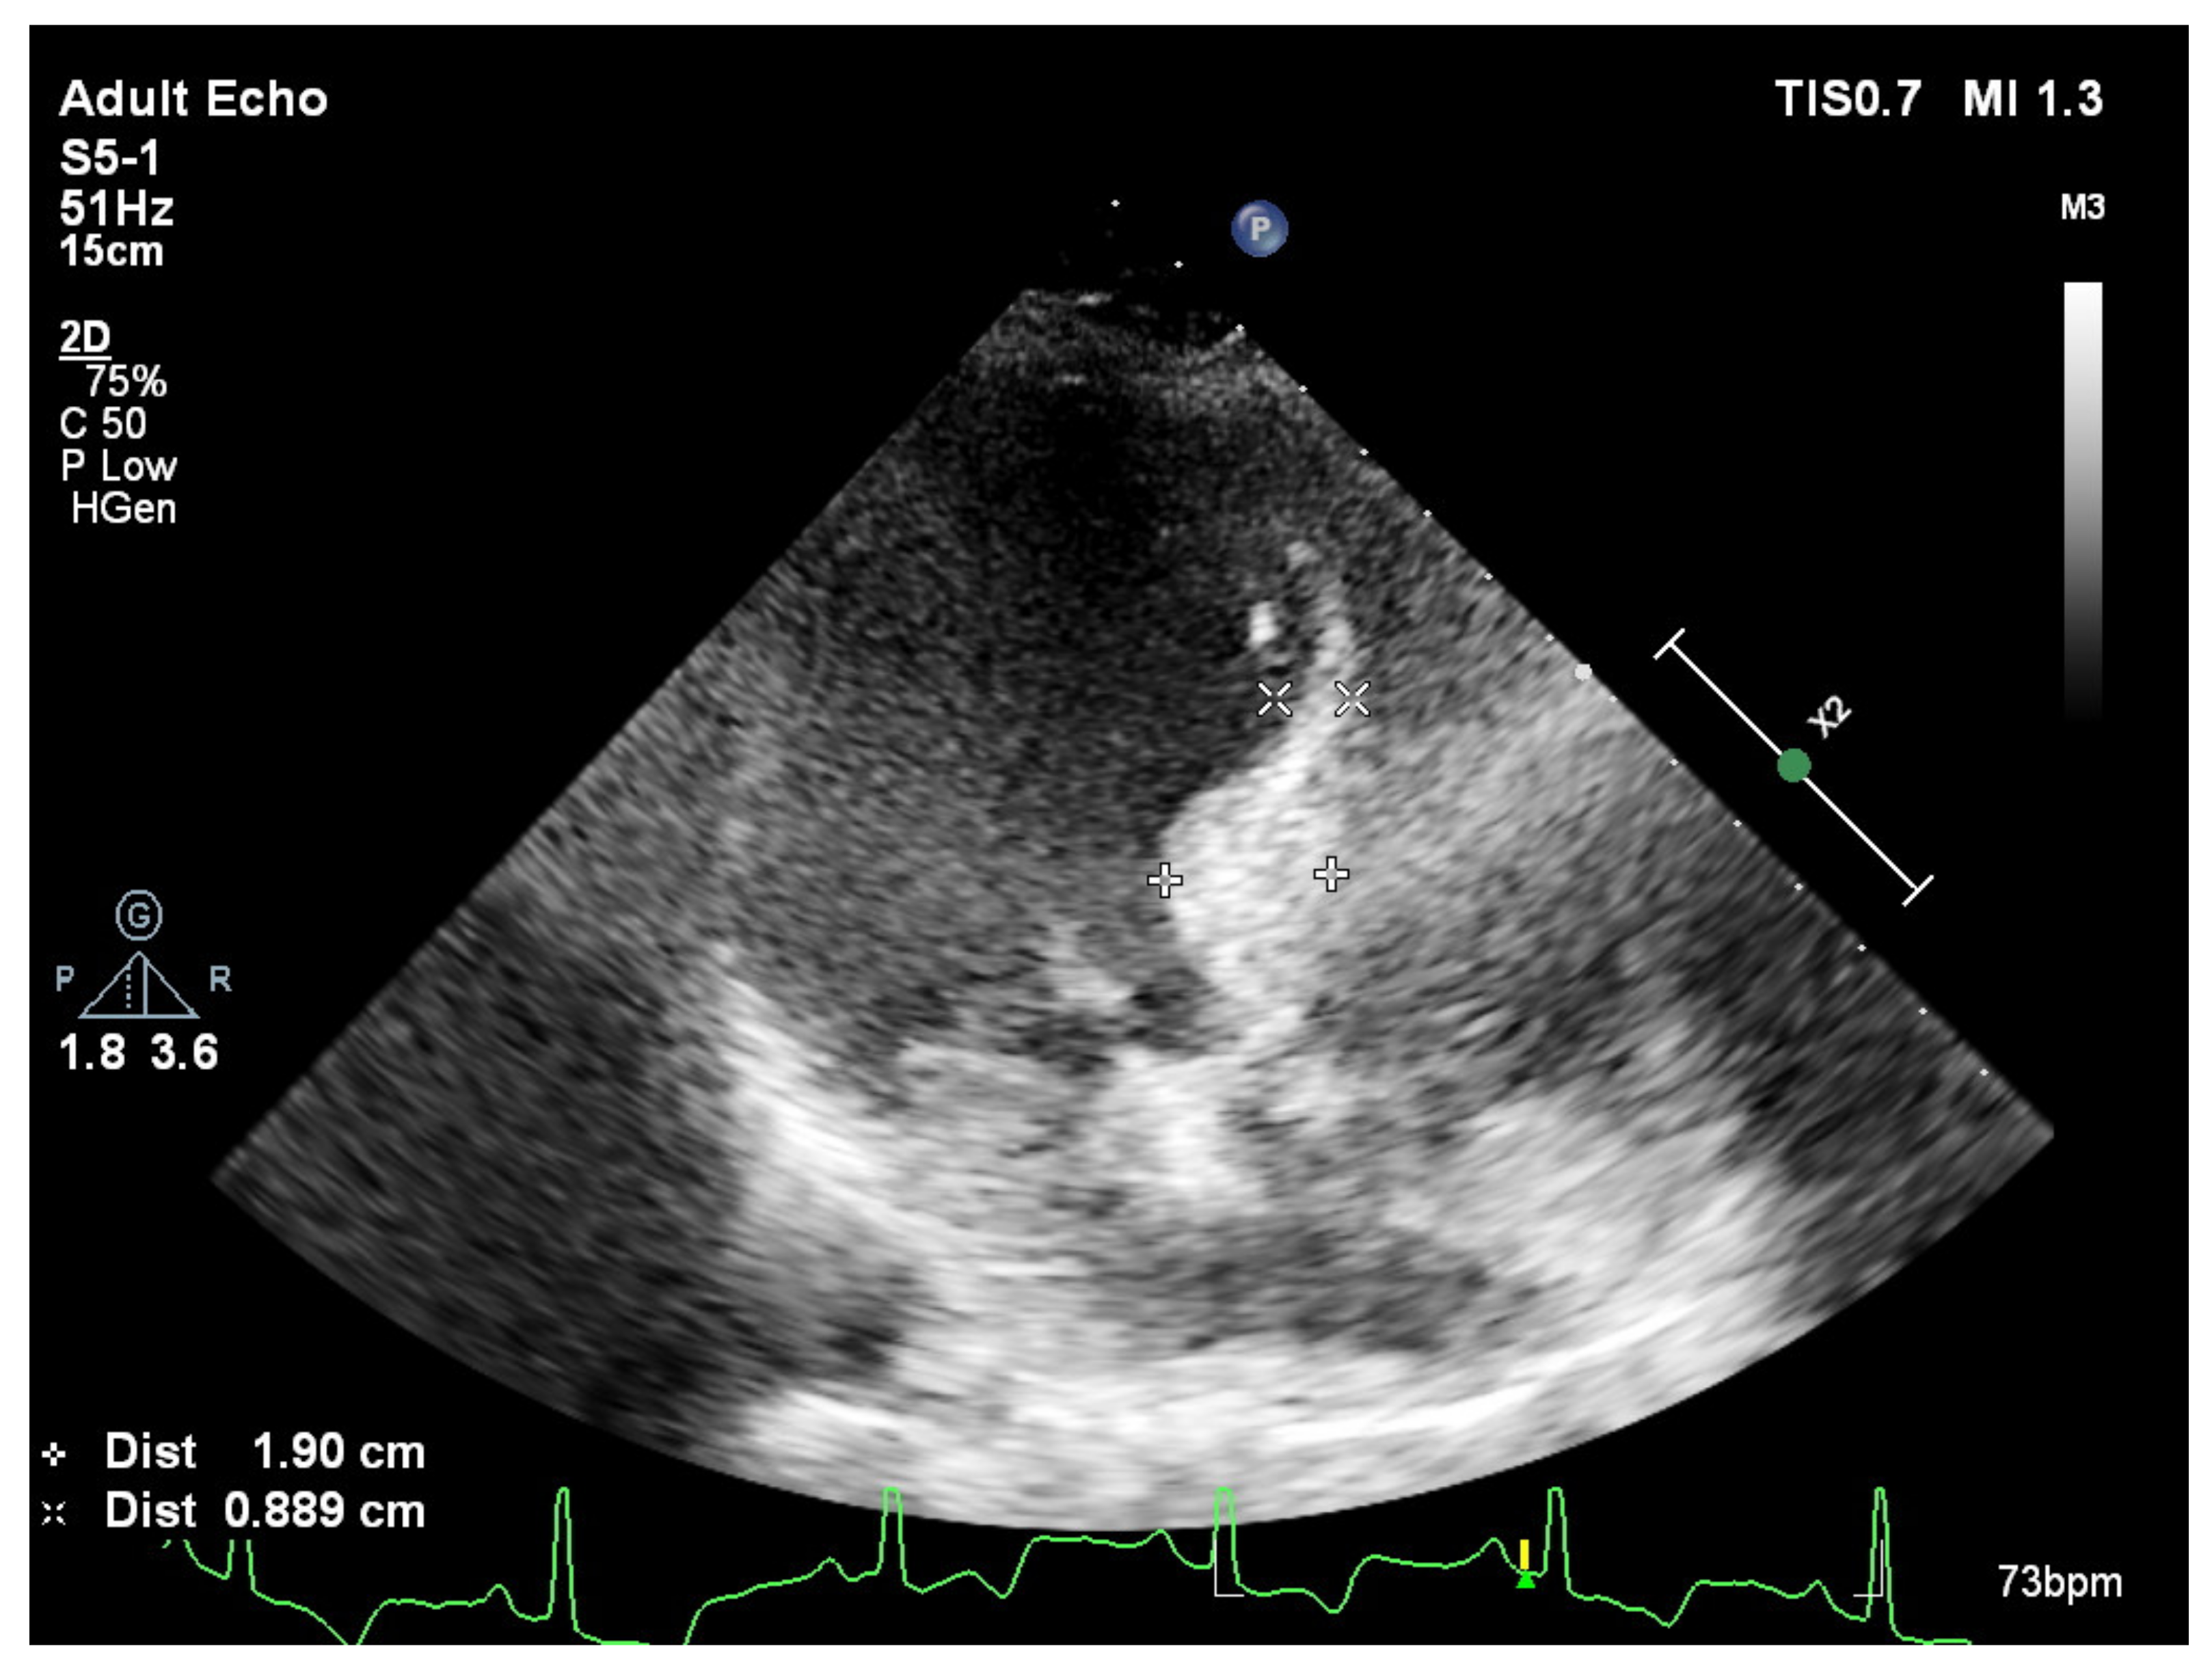

2. Basal Septal Hypertrophy and Clinic Observations

- Yalçin, F.; Topaloglu, C.; Kucukler, N.; Ofgeli, M.; Abraham, T.P. Could early septal involvement in the remodeling process be related to the advance hypertensive heart disease? Int. J. Cardiol. Heart Vasc. 2015, 7, 241–245. [Google Scholar] [CrossRef] [PubMed][Green Version]